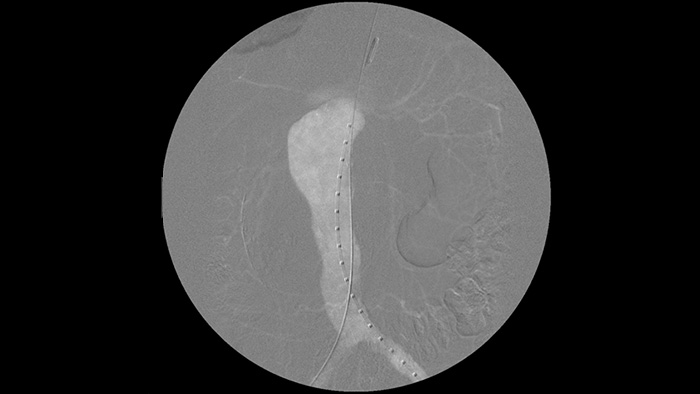

Es más fácil ver un cable guía en comparación con nuestro antiguo sistema. Ahora se puede ver la punta y el ángulo del cable que está dando vueltas, incluso con cables de 0,014 pulgadas.

Esto se debe a que Zenition compensa lo que es metal y lo que se mueve.

Dr. Ramón Vila Coll

Hospital Universitario de Bellvitge, Barcelona